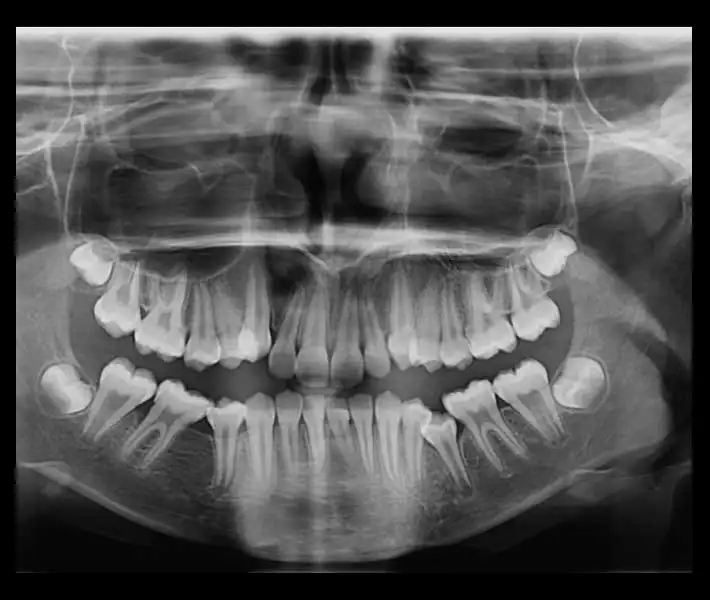

- رادیوگرافی پانورامیک